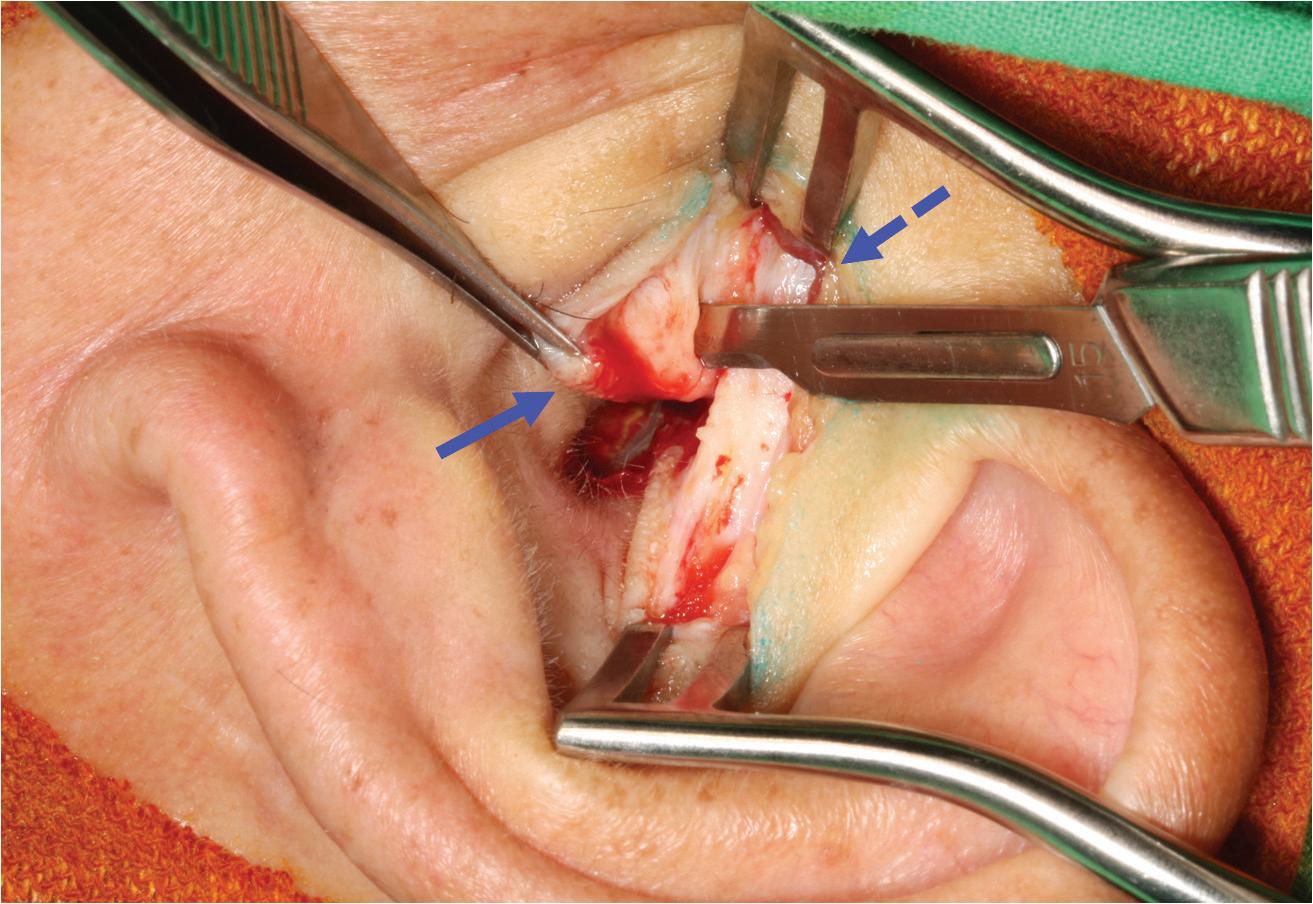

Considering the postsurgical history and the site of the mass, we diagnosed an iatrogenic EAC cholesteatoma. A whitish, spherical mass was identified on surgical exploration and was completely removed through the prior postauricular incision (figure 2). We subsequently performed canalplasty with EAC

defect reconstruction using fragments of conchal cartilage. The pathologist’s report revealed histopathologic features compatible with cholesteatoma. No evidence of recurrent disease was present during the 5-year follow-up.

Continued from page 340

from canalplasty with skin grafting for lesions confined to EAC, to canalplasty or canal-wall-up mastoidectomy with reconstruction of canal defects for lesions involving mastoid cells, to canal-wall-down mastoidectomy for lesions with large wall defects exhibiting mastoid erosion.4 If an EAC defect is to be reconstructed, as in our case, nonretractable materials such as cartilage make ideal grafts.

Myringoplasty is a commonly used and simple type of middle ear surgery associated with a low risk of postoperative, iatrogenic EAC cholesteatoma. However, it is important to ensure high accuracy when repositioning the skin flap. In addition, delicate and meticulous management of every step is essential to avoid trapping or implantation of epithelial debris under the skin flap or graft.

Figure 2. A spherical cholesteatoma sac is discovered during surgical exploration. Figure 2. Axial CT shows the dissected internal carotid artery (arrow) and calcified stylohyoid ligament (asterisk).

Figure 2. In this image, an intact eardrum without residual perforation can be seen on otoscopy 9 months postoperatively. Figure 1. These photographs show elements of the single endaural incision approach. A: An endaural incision is made. B: Both the temporalis fascia (dashed arrow) and tragal cartilage (arrow) grafts are harvested with a single incision.